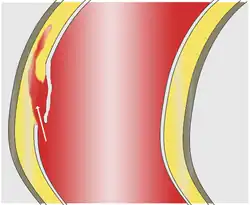

Quando a área deformada do vaso toma forma esférica, dá-se o nome de aneurisma saciforme ou sacular (de saco), ou quando tem forma alongada através do eixo principal do vaso, aneurisma fusiforme (de fuso).

O aneurisma sacular se desenvolve na parede de artérias com defeitos congênitos decorrente do aumento do fluxo sanguíneo ou pressão arterial, entre outras causas. É comum esses aneurismas se romperem, provocando hemorragia cerebral, causando até um acidente vascular encefálico hemorrágico (mais conhecido como derrame cerebral). É bastante perigoso e acarreta hemorragia com frequência.

Aneurisma é a dilatação anormal de um vaso sanguíneo causada pelo enfraquecimento das paredes do vaso, por trauma ou por doença vascular.[1] Pode ocorrer basicamente em qualquer vaso sanguíneo. É muito comum na população em geral, raramente causando sintomas ou problemas graves. Seu perigo está no fato de poder romper-se, resultando em hemorragia ou isquemia dos tecidos irrigados pela artéria atingida, sendo que a gravidade do dano depende da área irrigada pelo vaso afetado. O risco é maior caso o paciente seja fumante[2] ou tenha histórico familiar de doenças vasculares, problemas renais ou pressão alta.[3]